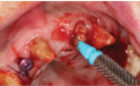

- N.B. Existing #17 to be converted to #16, existing #16 to be converted to #15 and 14, existing #26 to be converted to #24 and 25. Lastly #27 will be converted to 26.

- Prepare #17, 27 13, 11 and 23 and provisionalization.

- Extraction of #16, 12, 22 and 26. (Socket grafting #16, and 26 to preserve existing bone volume).

- Immediate implant placement in sites #12, 22, 14 and 24.